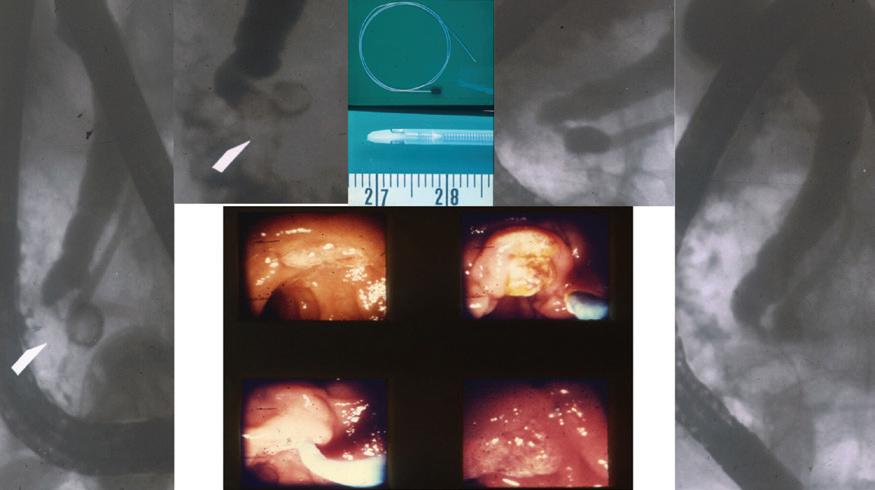

Malignant bile duct obstruction posed a problem to the ERCP physician in the 1970s. Endoscopic cannulation of the bile duct introduced bacteria-laden contrast dye into an obstructed biliary tree, and endoscopic sphincterotomy alone would not provide adequate biliary drainage except in the most distal bile duct or ampullary cancers. Percutaneous transhepatic methods for biliary drainage were commonly employed preoperatively in patients with deep jaundice or for palliation, and the first report of a percutaneous transhepatic cholangiography (PTC)-guided internal bile duct prosthesis was reported by Burcharth et al. in 1979.20 In 1980, the ERCP groups in England (Laurence and Cotton21) and Germany (Soehendra and Reynders-Frederix22) reported the early cases of internal decompression of malignant biliary obstruction by ERCP-directed biliary endoprosthesis placement (Fig. 1.4). The initial methods relied on “borrowed” technology and reported the uses of a 7-Fr nasobiliary drain fashioned from an angiographic catheter and a “pigtail” stent cut from a 7-Fr Teflon catheter. Over the next 30 years, with the aid of industry and ingenuity, biliary endoprosthesis design continued to advance from the back table of the craftsman/endoscopist to the precision engineering of multisized polyethylene stents and

FIG 1.4 ERCP-directed bile duct drainage using biliary stents was introduced by Soehendra and Reynders-Frederix from Hamburg, Germany, in 1979, adding to the armamentarium of therapeutic ERCP. The team used a 20-cm-long, 7-Fr radioopaque angiographic catheter with 12 side holes inserted over a guidewire with a single pigtail that allowed it to be fixed inside the bile duct. (Photo courtesy Dr. Peter Cotton, Medical University of South Carolina.)

In the bottom middle is the limited field of view of the duodenal papilla on the left and the papilla after sphincterotomy on the right. (Photo courtesy Dr. Peter Cotton, Medical University of South Carolina.)